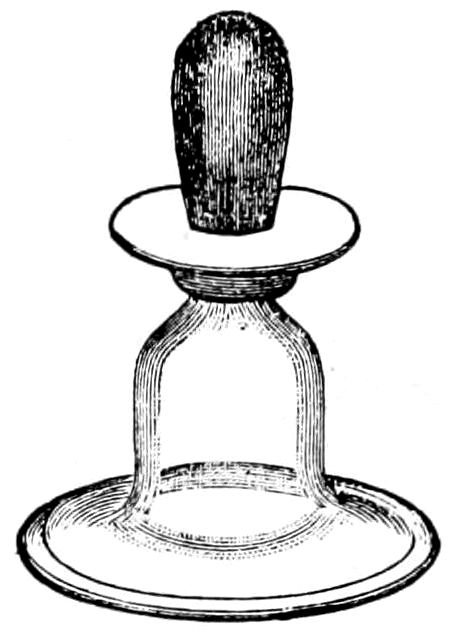

| |

| 109. |

A standard nipple shield |